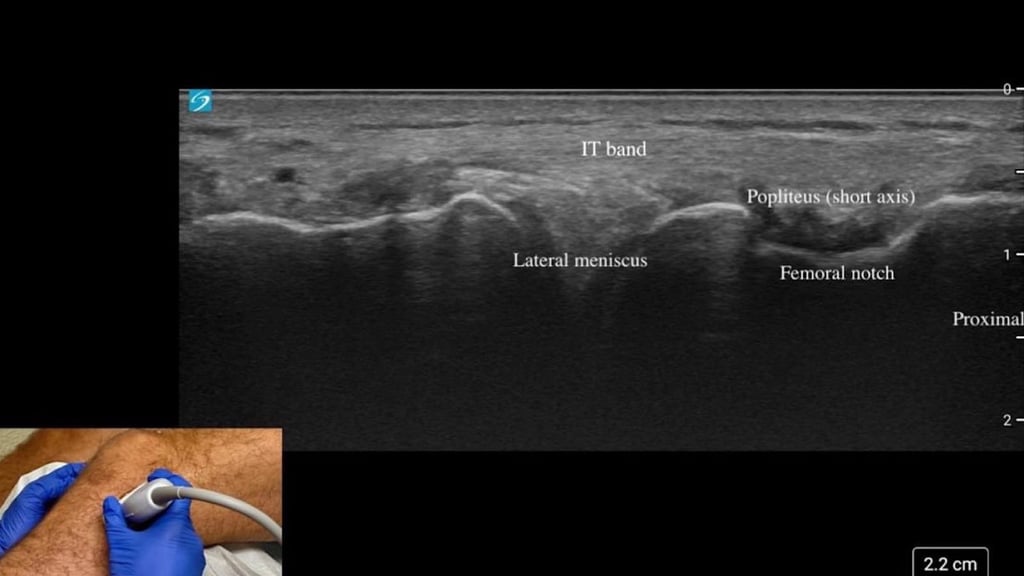

échographie articulaire

IRM du genou

Ces examens permettent d’identifier la cause du gonflement.